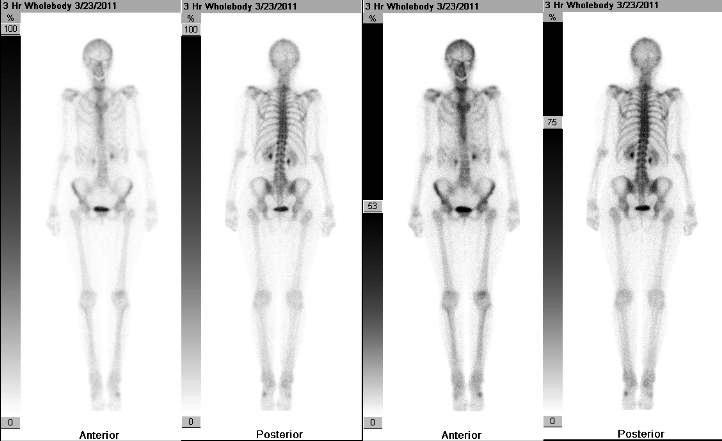

經過比對之後覺得它比較像是一張「全身骨骼掃描」

(正常的骨骼掃描大概長這樣)

大多是黑白的,不過殿下家的影像系統可能比較高級些,有彩色色階顯影XD

雖然不太清楚,但從這張掃描可以推論一些訊息:

1. 骨骼掃描會顯現出骨頭近期代謝最旺盛的地方,例如受傷骨折、感染、或長腫瘤等。

醫院裡最常拿來尋找全身轉移的癌症@@ 但劇情沒有提這種方向,因此我覺得,

這邊應該是拿來幫Bucky做了一個全身的傷勢評估

(畢竟過去幾十年都在做高受傷風險的工作)。

2. 但光做骨骼掃描會看不出舊傷(已經完全癒合的傷),

所以我覺得應該有配合做了全身的斷層掃描或磁振造影,把新舊傷做個綜合評估。

3. 左肩關節的地方,影像只有到肩胛骨,沒有左手臂的骨頭,

可推測Bucky的左手是受重傷之後被完全截除,肩關節應該也是金屬義肢的一部分。

而在和鋼鐵人一戰斷掉的左手,

因為金屬在骨骼掃描上是看不到的,這邊修正一下,有兩種可能:

(1)機械關節還在,之後需要的時候再像裝義肢一樣把手臂裝上去

(2)整個關節開刀拿掉了,所以下次需要裝就要再手術一次。

4. 覺得影像上兩邊膝蓋和肋骨的顯影有點強...顯示最近有受傷過,

是不是最近很努力地各種逃跑追趕和戰鬥,過度使用到都快退化性關節炎了> <

(當然也可能是99歲老人家的退化現象XDD

肋骨的話... 比較少看見這種顯影模樣

只能說多次戰鬥中說不定造成了一些肋骨的小骨裂 (感覺很痛> <